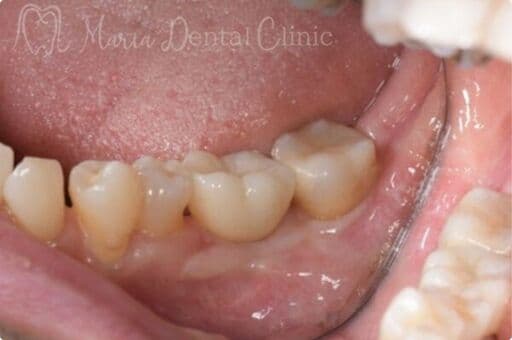

サイナスリフトの症例

【症例】サイナスリフトで骨を増やし、奥歯の支えを回復したインプラント治療

本症例の患者様は、右側の歯を抜歯した後そのまま放置していたことで噛み合わせが大きく乱れ、右上の歯周病が進行して抜歯に至りました。抜歯後は上顎洞に近接して骨量が著しく不足していたため、サイナスリフトによって新たな骨を増やし、インプラントを支える土台を再建しました。十分な骨量を確保することで、奥歯の咬合支持を回復した症例です。

| 治療内容 | サイナスリフト、インプラント、矯正治療 |

|---|---|

| 治療期間 | 10ヶ月 |

| 治療回数 | 4回(他、抜糸、術後3ヶ月後、1年後の経過観察等を除く) |

| 治療費用 | 3,300,000円(税込、サイナスリフト他、矯正治療を含む) |